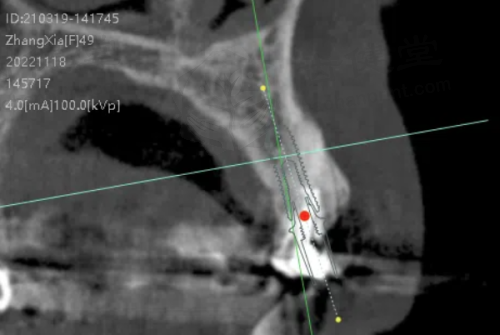

在设备方面,医院配备了精良的口腔医疗设备,有CBCT机、全景机、超声洁治器、铸造机、切割装置、根管测量仪、根管填充器、激光设备、电动吸引器和口腔内窥镜等,为精细诊疗提供了有力保护。www.haohanprint.com